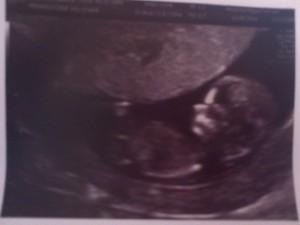

Semana 12: primera ecografía… por fin!!

Aquí está la pulgueta, aún no sabemos si será chica o chico, pero que más da, todo está bien, yo me encuentro mejor… La verdad que no recordaba tan chula la primera ecografía. Recuerdo que sí que me sorprendió que se veía bien, pero esta vez me pareció una pasada. Se veía como movía los brazos, tenía una pierna doblada y la otra con el pie “hacia la cámara” y se distinguía la planta del pie, además se veía como se movía perfectamente (que aproveche ahora que aún tiene espacio). Para variar las explicaciones escasas, tampoco hay mucho que explicar: cabeza, extremidades, sonido del corazón, comprobación de anomalías cromosómicas… todo bien, pues para casa. Y más contenta que unas castañuelas!